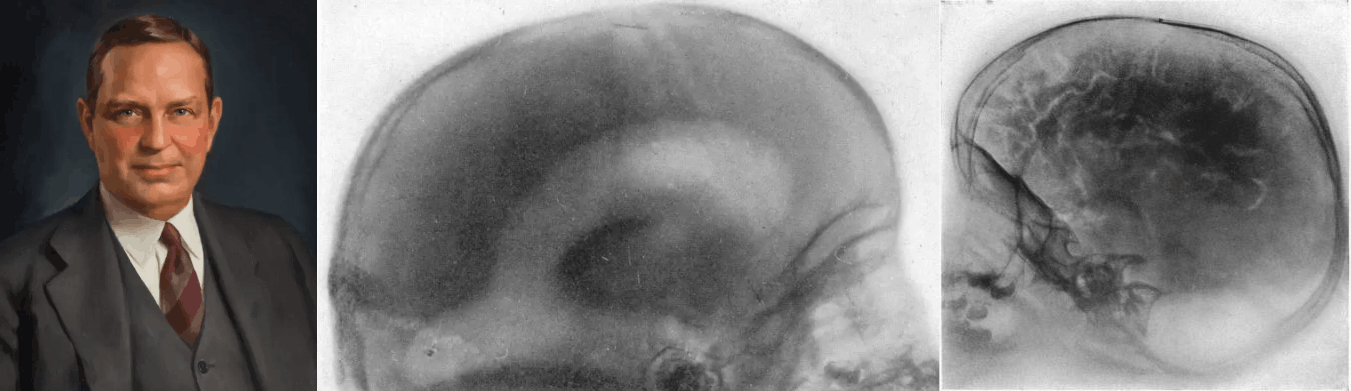

Рисунок 1. Основные вехи в долгой истории нейротехнологий. ~5000 лет до н.э.: Следы трепанации обнаружены на 10% черепов каменного века, преимущественно у взрослых мужчин. V в. до н.э.: Древнегреческий философ Алкмеон Кротонский первым выдвинул идею, что мозг — субстрат разума и ощущений. II в. н.э.: Римский врач Гален систематизировал знания об анатомии мозга, описав мозжечок, желудочки и черепно-мозговые нервы. 1543: Андреас Везалий опубликовал «De Humani Corporis Fabrica» — первый достоверный атлас анатомии человека, основанный на реальных вскрытиях. Раздел о мозге исправил множество ошибок Галена. 1791: Луиджи Гальвани в экспериментах с лягушачьими лапками доказал, что нервы и мышцы проводят электрический ток. Открытие «животного электричества» заложило основу всей нейрофизиологии. 1848–1871: В 1861 г. Поль Брока выявил моторный центр речи в левой лобной доле. В 1871 г. Карл Вернике описал сенсорный центр в левой височной доле. 1873: Камилло Гольджи открыл «черный метод» окраски нейронов нитратом серебра. Сантьяго Рамон-и-Кахаль доказал, что нейроны — отдельные клетки, а не единая сеть. 1895: Вильгельм Конрад Рентген открыл рентгеновское излучение. Уже через год врачи использовали рентгенографию черепа для диагностики переломов и инородных тел. 1912 / 1924: В 1912 г. советский физиолог В.В. Правдич-Неминский впервые зарегистрировал ЭЭГ с черепа собаки. В 1924–1929 гг. немецкий психиатр Ганс Бергер записал ЭЭГ человека, открыв эпоху функциональной диагностики мозга. 1927: Португальский невролог Антониу Эгаш Мониш разработал метод введения йодсодержащего контраста в мозговые сосуды (церебральная ангиография). 1937: Нейрохирург Уайлдер Пенфилд составил детальные карты функциональных зон коры и изобрел «гомункулюса» — модельного человечка, демонстрирующего непропорциональность функционального представительства частей тела в коре больших полушарий. 1948: Норберт Винер постулировал, что живой организм и машина используют одни принципы обратной связи и электрической передачи информации. Это концептуально открыло путь к нейроинтерфейсам. 1961: Уильям Хаус и Джон Дойл имплантировали первые электроды в улитку двух глухих пациентов. Это первый в истории нейропротез, восстанавливающий утраченное чувство через прямую электрическую стимуляцию нерва. 1972: Годфри Хаунсфилд и Аллан Кормак разработали компьютерный томограф. Началась эра нейровизуализации. 1973 / 1982: Пол Лотербур предложил использовать ЯМР для построения изображений (1973). Питер Мэнсфилд усовершенствовал алгоритмы. С 1982 г. начато коммерческое производство МР-томографов. 1985: Энтони Баркер с коллегами разработал метод транскраниальной магнитной стимуляции. 1990: Японский биофизик Сэйдзи Огава открыл принцип BOLD-контраста (зависимость МР-сигнала от насыщения гемоглобина кислородом). Это стало основой функциональной МРТ. 1998: Невролог Филипп Кеннеди имплантировал первый нейрочип в мозг парализованного пациента Джонни Рэя. Началась эра инвазивных нейроинтерфейсов «мозг–компьютер». 2014: На открытии ЧМ по футболу в Рио-де-Жанейро парализованный Джулиано Пинто ударил по мячу с помощью экзоскелета, управляемого ЭЭГ-сигналами с поверхности головы. 2024: В январе 2024 г. компания Neuralink Илона Маска имплантировала первый беспроводной нейрочип пациенту Ноланду Арбо. К 2026 г. чип использует 21 человек.

Иллюстрация Елены Беловой